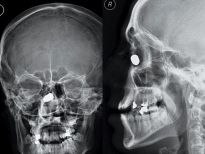

Şoke eden röntgen filmleri

Bu röntgen filmleri görenleri şaşkına çeviriyor!